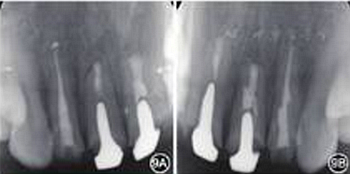

见图8,图9,图10,图11。分别于术后3、6个月时复查根尖X线片,8个月时复查锥形束CT并分别进行临床检查。复查结果显示根尖病变已愈合,根尖无明显低密度影。临床检查叩诊正常,无松动,牙龈位置无明显变化。

图9 6个月复查患者根尖X线片 A:根尖病变愈合;B:根尖病变接近愈合